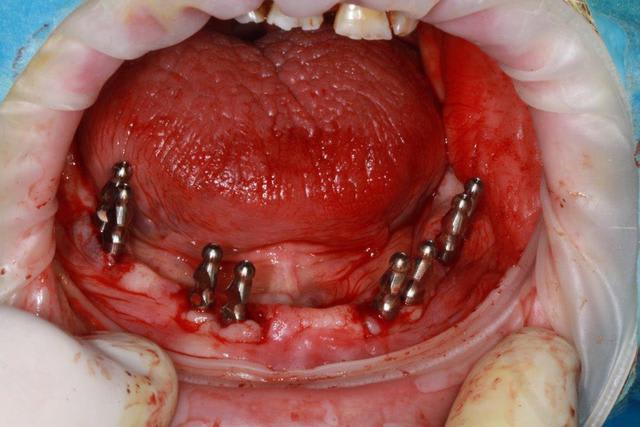

essayage et pose prothèse du bas et ceram 12/22

Pour le bas, armature métal transvissée, recouverte d'Emax press, et fausse gencive.

avantage, en cas de problème il suffit de percer l'emax pour dévisser l'ensemble, et sinon aspect fini très propre, pas de trace des puits de vissage.

autre avantage en cas de fracture de la ceram, il suffit de changer l’élément concerné.

dans ce cas les emax sont réalisés après la fausse gencive.

et pour répondre à ta question brossage ceramik, l'espace gencive/fausse gencive est suffisant pour permettre un très bon brossage.

pour le haut 12 sera fracturé et donc extraite.